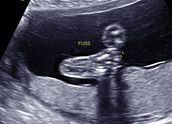

Ich bin Martina und ähm... joa... das erste mal Schwanger.. Total aufgeregt... Bin 25 Jahre jung und der werdende Papa ist vorgestern 27j. geworden und klebt an mir xD .. ne quatsch.. er freut sich riesig auf unser Würmchen... ;) Letzten Freitag hatte ich meinen ersten FA - Termin und laut Arzt war ich dort in der 6 + 5 SSW ... Heute hab ich mein Mamipass bekommen und total stolz, auf die Zukunft :) Unser Würmchen war beim ersten Termin stolze 10,2mm klein... Ohje, was war das schön, als das Herzlein bubberte ;) ... Ende Februar 13 soll des Würmchen kommen... Sooo... nun hab ich aber genug getippselt.. Freu mich über evtl Nachrichten zum austauschen von erlebnissen in der Schwangerschaft... LG Tini